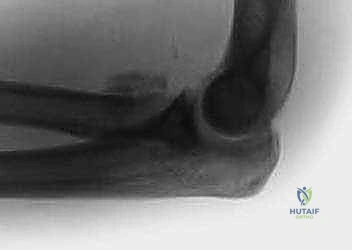

- الأشعة السينية (X-rays): يتم أخذ صور بأوضاع مختلفة (أمامي خلفي، جانبي، ومائل) لرؤية الكسر بوضوح. أحياناً يكون الكسر دقيقاً جداً ولا يظهر إلا من خلال علامة "وسادة الدهون المرفوعة" (Positive Fat Pad Sign) التي تشير إلى وجود نزيف داخل المفصل.

- الأشعة المقطعية (CT Scan): في حالات الكسور المفتتة أو المعقدة، يطلب الدكتور هطيف إجراء أشعة مقطعية ثلاثية الأبعاد (3D CT) لبناء تصور هندسي دقيق للكسر، مما يساعده في تخطيط العملية الجراحية واختيار الشرائح والمسامير المناسبة قبل دخول غرفة العمليات.